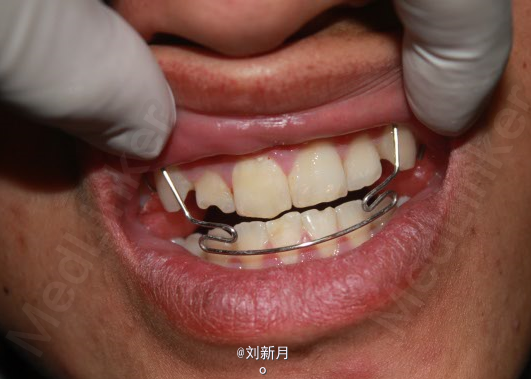

主诉:地包天求矫治 既往史:无矫治史,无牙科治疗史,无外伤史,无过敏史,无口腔不良习惯,无家族遗传史 口腔检查:恒牙列,A7-B7;C7-D8。牙齿排列整齐 尖牙磨牙III类关系,前牙反合 中线对正 面型为凹面型 关节无弹响无压痛

口腔检查 前牙反覆合,反覆盖 拍头颅侧位片,曲面断层片

诊断:安氏III类错合 矫治计划 1.前期活动矫治,后期MBT矫治技术 2.非拔牙矫治 3.利用低位唇弓解除反合,后期排齐整平牙列 4.矫治结束后尖牙,磨牙,覆合覆盖基本正常 5.面型有所改善